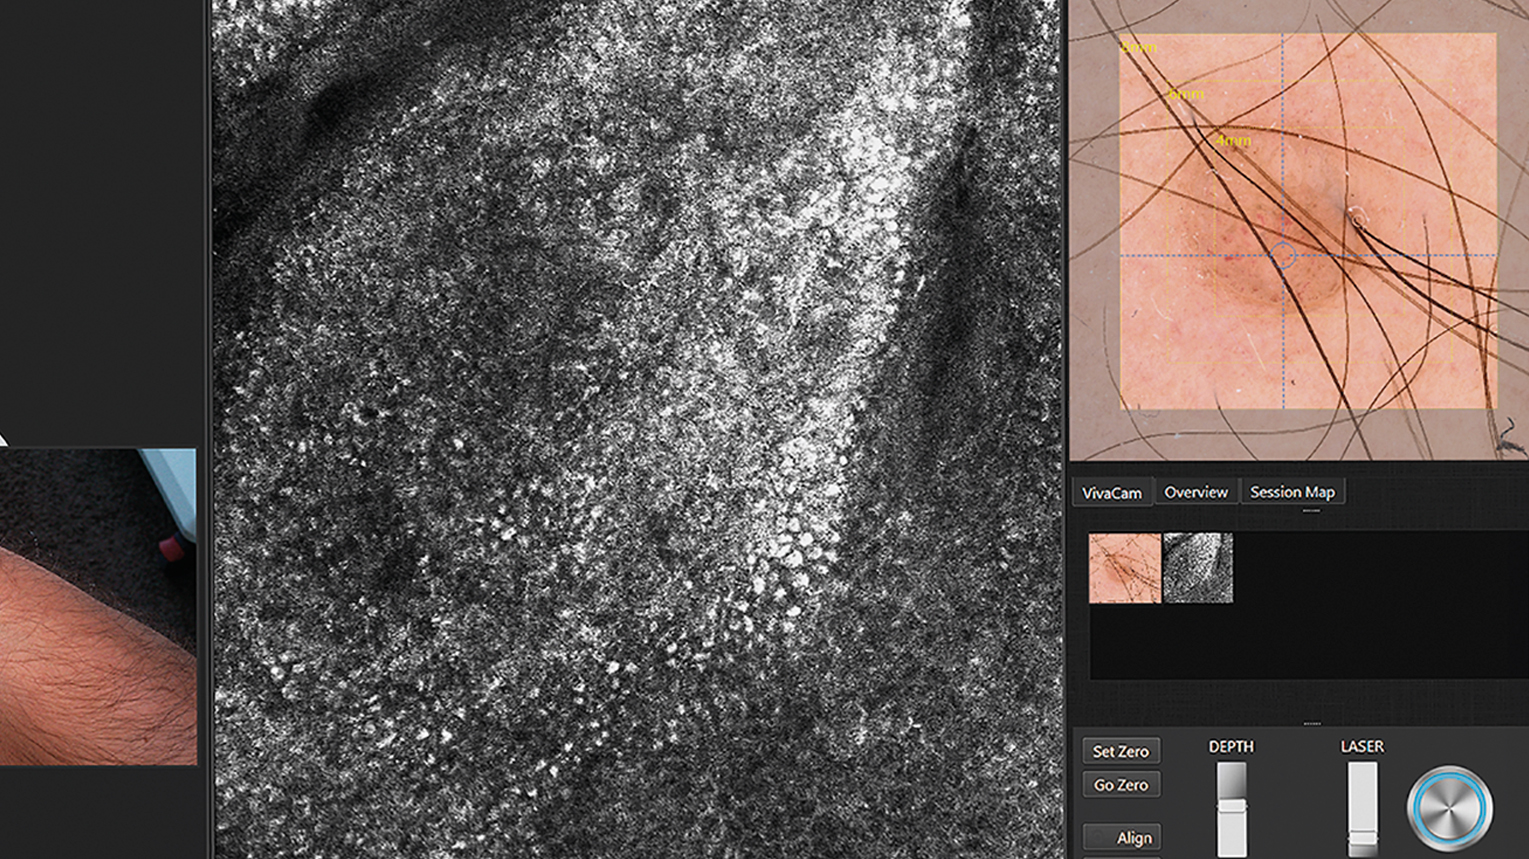

In Vivo examinations with the VivaScope technology using confocal laser scanning microscopy (CLSM) allow for an optical biopsy using a non-invasive procedure. See the different skin layers of your patients in real time.

All images courtesy of Prof. Dr Elke Sattler, Dr Martina Ulrich, Prof. Dr Julia Welzel

Different System Configurations:

Make it your VivaScope. For your every day work. Learn more about the different system configurations.